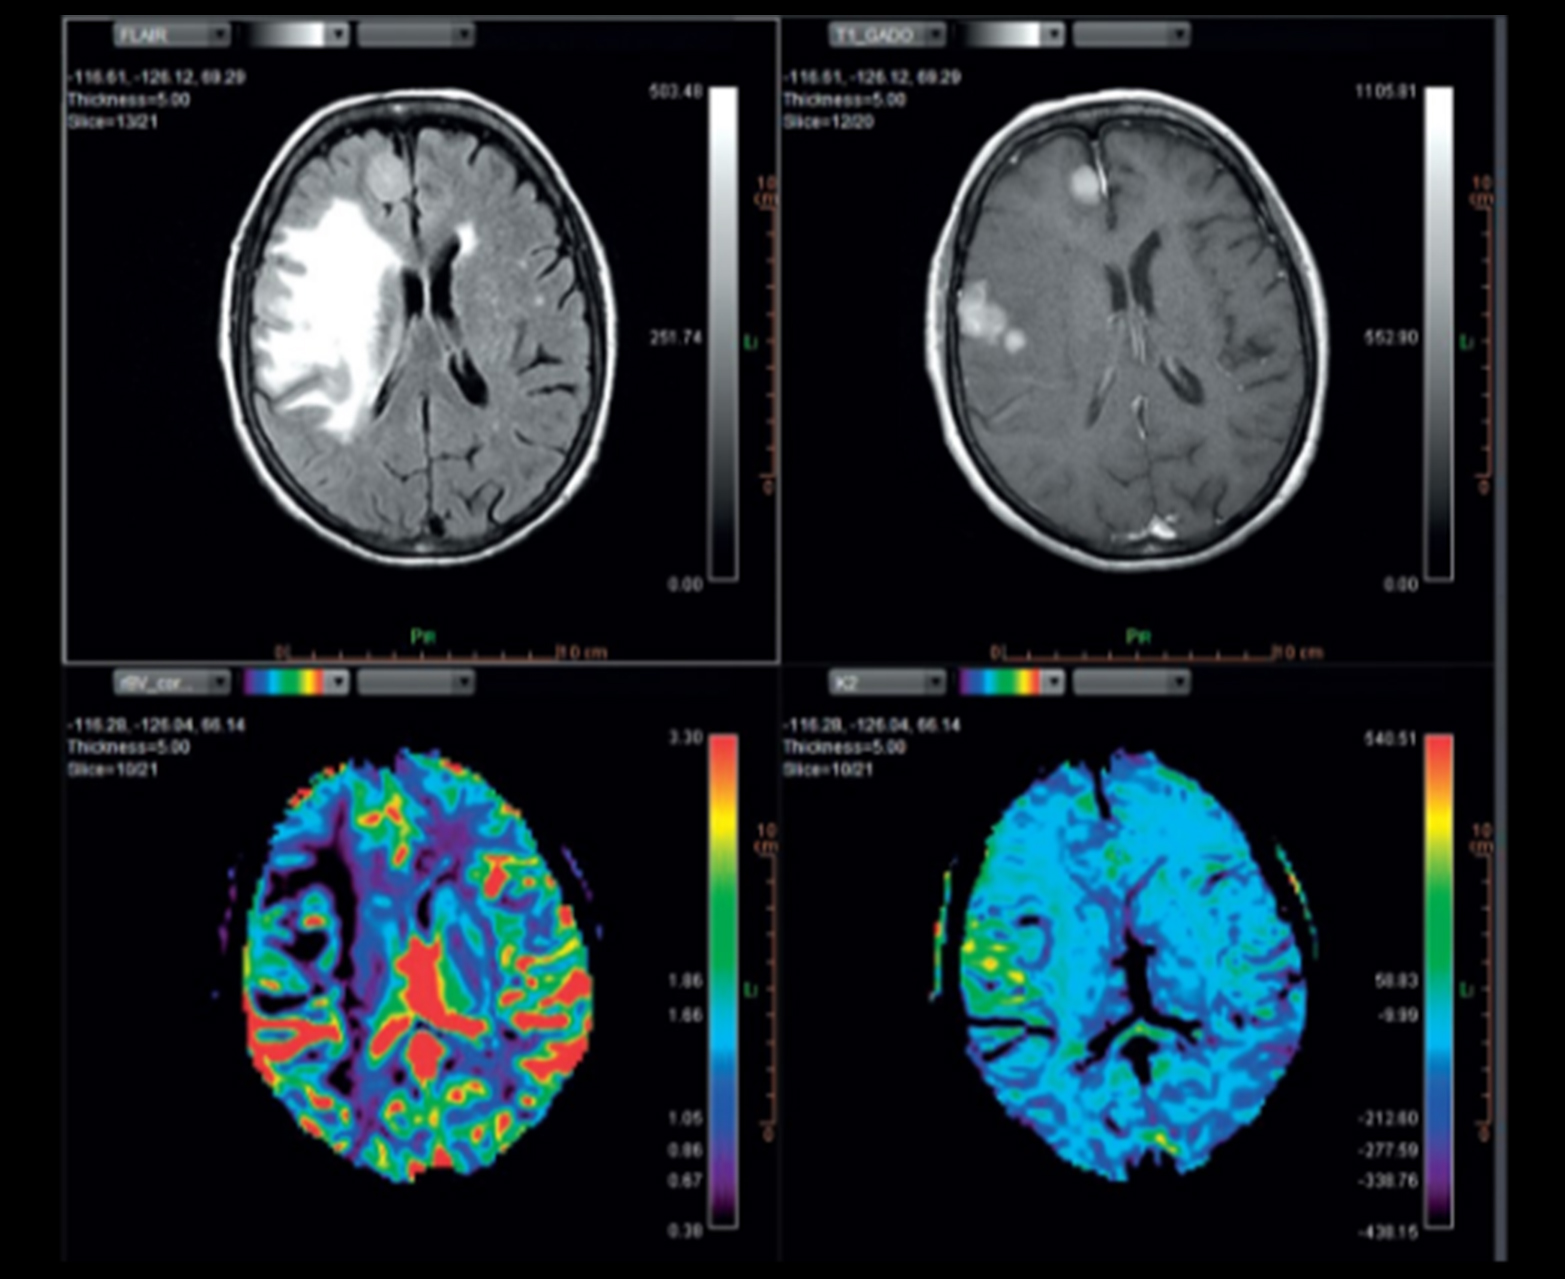

Многопараметрическое настраиваемое отображение карт диффузии и перфузии, включая карты rCBV_corrected и K2